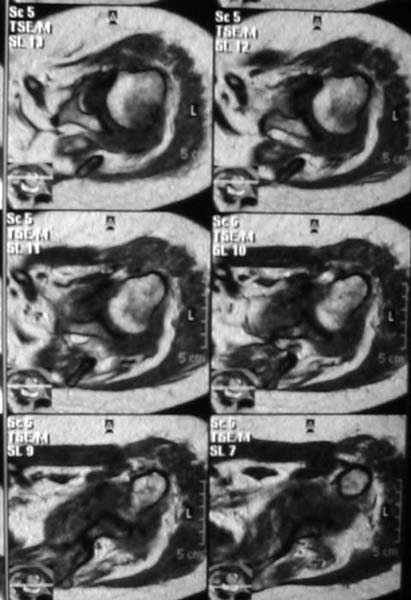

В приложенном файле - МРТ изображение. Более информативно, чем предыдущий вариант? менее? или также?

Все-таки, должен признать, что такие снимки - суррогат. Информативность чуть-чуть лучше, за счет большего размера. С учетом сложных топографо-анатомических соотношений необходимо иметь картину всех срезов, и смотреть их поочередно, иначе не создается целостной картины, а также иметь возможность манипулировать контрастом. Вот если б снимки были в DICOME - тогда от интерпретации было бы не отвертеться -)

1. На рентгене - нижний подвывих плеча и очаг остеолиза суставного бугорка с четкими контурами (вдавленный перелом на фоне остеопороза ? доброкачественная опухоль? аваскулярный некроз ? (хотя ни разу не слышал об аваскулярном некрозе плеча..)

2.выраженный выпот в полости сустава

3. Сказать о связках и сухожилиях что-то при снимках в таком режиме не берусь.